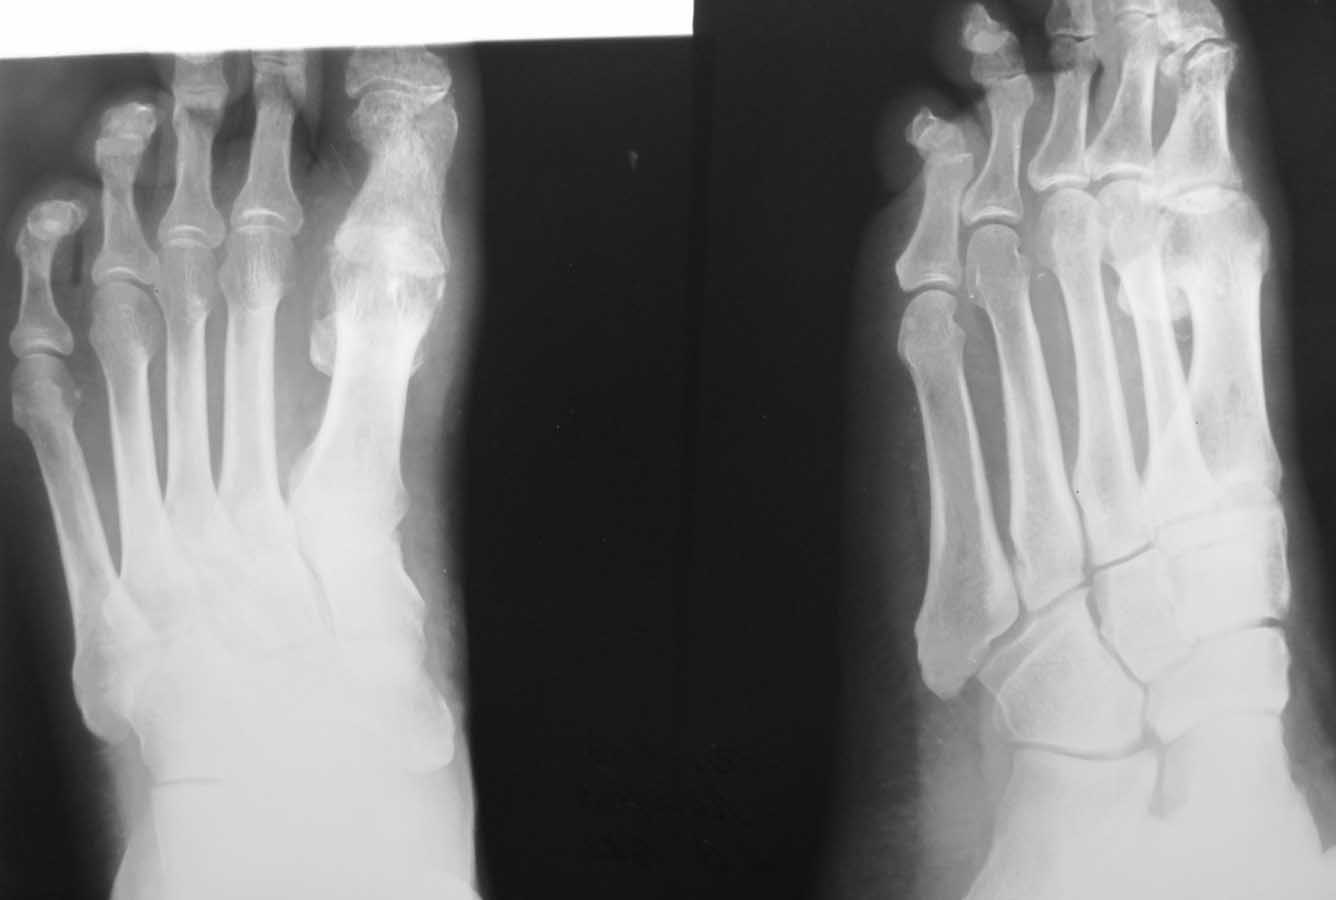

Здравствуйте, коллеги. Помогите с тактикой дальнейшего лечения.Мужчина 52 года, активный физически. В марте 2012 оперирован по поводу ДОА плюсне-фалангового сустава 1 пальца, сделана резекция основания основной фаланги и остеофитов головки плюсневой кости. Послеоперационное лечение: массаж, физиотерапия. В настоящее время беспокоят сильные боли в суставе, сохраняется ограничение движений. Дальнейшая тактика: артродез ПФС?, Эндопротезирование ПФС?, повторная резекция основной фаланги? Мнения наших коллег разделились. На фотографиях: вид стопы в настоящее время, рентгенограммы до операции, после операции, в настоящее время. Прошу прощения за неважное качество снимков.

Просто удаление остеофитов не приводит к желаемому результату. Необходимо резецировать до 1/3 суставной поверхности головки, основание очистить от остеофитов с тыльной поверхности.

Любой из рассматриваемых Вами вариантов имеет право на жизнь. Наиболее вероятная причина болей - слишком экономная резекция фаланги: адекватная декомпрессия сустава не достигнута. Протезирование 1 ПФС у молодого активного физически мужчины предполагает ревизию уже через несколько лет. Так что артродез или повторная резекция основной фаланги - равнозначные оптимальные варианты.

У больного 1 плюсневая кость длинее 2 (в этом основная причина развития патологии). Молодой активный пациент с высокими требованиями, считаю, что эндопротезирование более оптимальный вариант. Эндопротезирование явлеяется альтернативой артродезу (который можно сделать всегда, но движений не будет уже) и артропластике (после которой рецидив будет очень быстро). Эндопротезированием можно восстановить и объем движений и функцию.

Причинами неудовлетворительного результата могли стать следующие: 1) недостаточная величина резекции основной фаланги и 2) "стирание" оставшегося хряща головки 1 ПК опилом фаланги. В своей практике обычно убираем больше кости (примерно 1/4 - 1/3 длины фаланги), опил моделируем, укрываем лоскутом капсулы или Артелоном (специальный биодеградируемый скользящий материал).